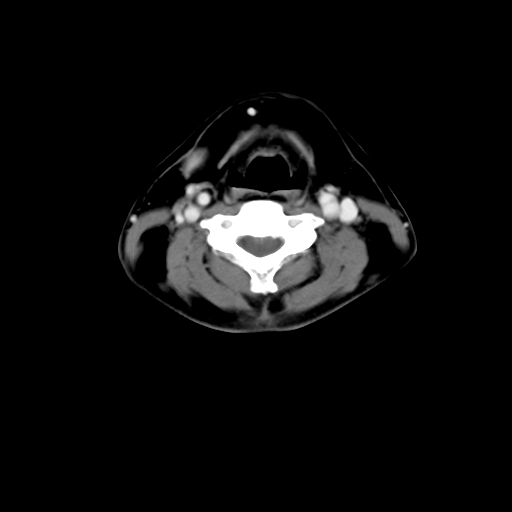

标题: CT24019:男,45岁,发现颈部肿物5个月。 [打印本页]

男,45岁,发现颈部肿物5个月,彩超示:双侧颈部及下颌部软组织增厚。

考虑双侧颈项部良性对称性脂肪增多症。

双侧颈项部脂肪沉积